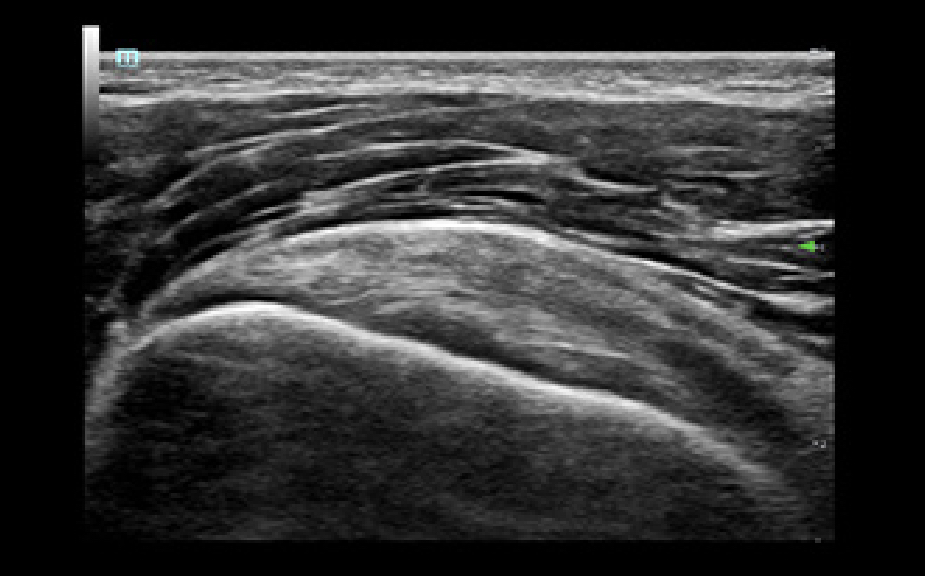

Solution de ponction par un seul op├®rateur